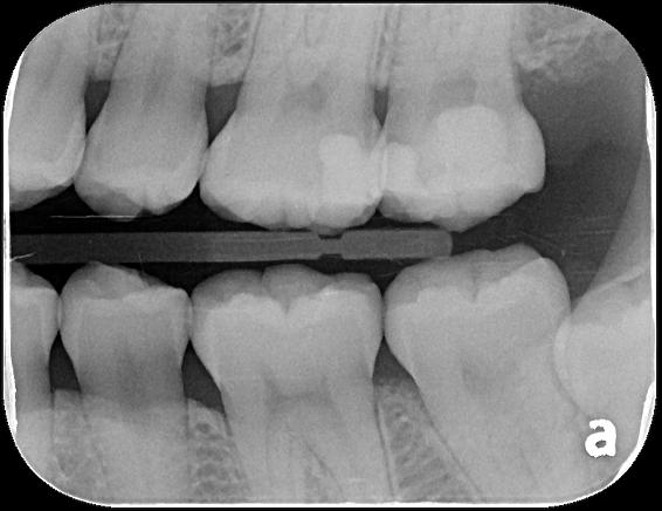

X光可見大臼齒內有蛀洞